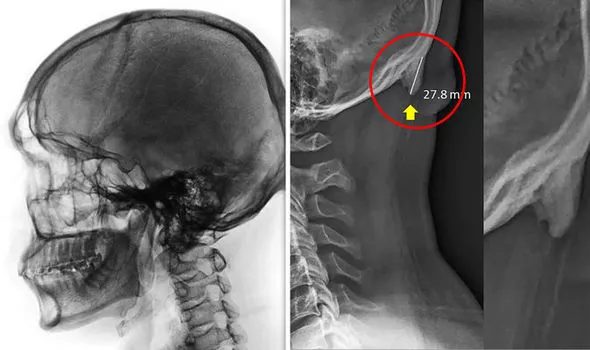

Các nhà nghiên cứu đã tiến hành quét tia X ở hơn 200 người trẻ, tìm thấy các gai xương hay còn được gọi là enthesophytes xuất hiện ở sau đầu. Họ cho biết, hiện tượng phát triển bất bình thường này là do áp lực dài hạn mà bộ xương đã phải chịu vì hành vi nghiêng đầu về phía trước quá lâu khi con người sử dụng điện thoại smartphone trong thời gian dài.

Tiến sĩ David Shahar nói: “Chúng tôi đưa ra giả thuyết rằng áp lực tăng liên tục ở phần cơ sau đầu là do trọng lượng bị dồn lên khi đầu nghiêng về trước để sử dụng các thiết bị công nghệ hiện đại trong thời gian dài”.

“Việc nghiêng đầu về trước sẽ dẫn đến sự dịch chuyển trọng lượng từ xương cột sống tới các cơ sau đầu và cổ”.